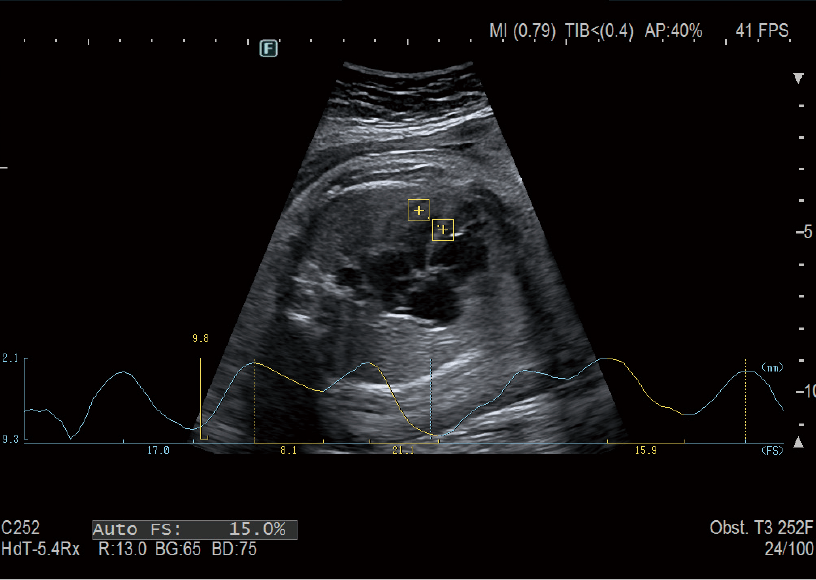

AutoFHR+ calculates the fetal heart rate automatically by tracking the movement of the fetal heart from a B mode image in real time. This function is available on both transabdominal and transvaginal transducers, so the fetal growth can be assessed from early gestation onwards. AutoFS tracks fetal heart movement from a B mode image and automatically calculates %Fractional Shortening (%FS). Unlike the M-mode method, AutoFS is not affected by a change in the fetal position, so heart movement can be measured.